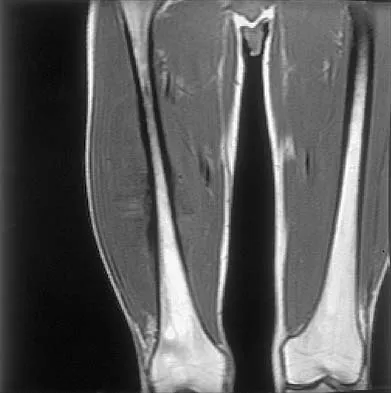

Figures 35a and 35b show the axial T2-weighted and coronal T1-weighted MRI scans of a patient who has enlargement of the right thigh. What is the most likely diagnosis?

Explanation

The images show a large, almost circumferential, mass surrounding the diaphysis of the femur. The intramedullary signal is normal with minimal cortical destruction, both findings that should be abnormal in conventional osteosarcoma and Ewing's sarcoma. There are very low-signal striations representing osteoid formation that would have a sunburst radiographic pattern. This indicates an osteogenic lesion. Myositis ossificans is not indicated because studies would reveal zonal ossification starting in the periphery rather than the more central pattern seen in this patient. This appearance is typical for periosteal osteosarcoma.